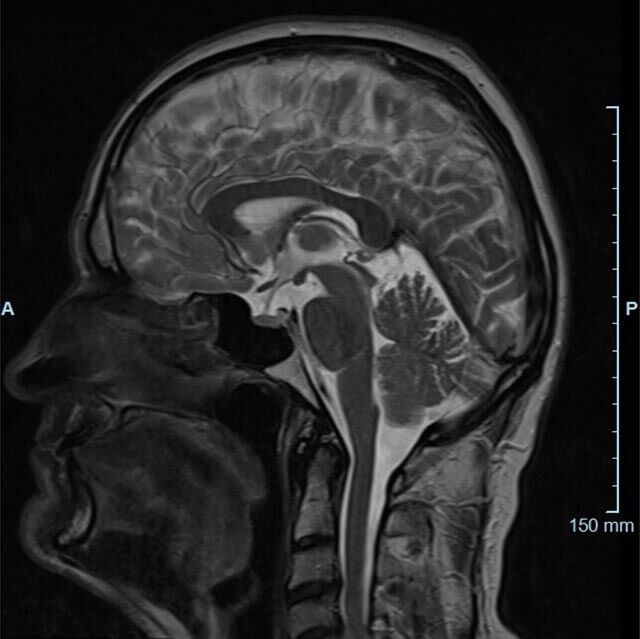

Kopf/Hals

Kopf

• akute Schlaganfalldiagnostik und chronische Durchblutungsstörungen

• entzündliche Prozesse des Gehirns oder der Gesichtsweichteile

• Tumore, ggf. mit Spektroskopie

• Abklärung Schwindel, zentrale Sehstörung, Kopfschmerz

• Metastasenverdacht

Halsgefäße

• Multiple Sklerose

• Abklärung Hirnnerven, Schädelbasis inkl. Hypophyse

• Abklärung Kleinhirn, Hirnstamm, Halsmark

• intrakranielle Gefäße (Abklärung Verschluss, Stenose, Aneurysma)

• Halsgefäße zur Therapieplanung (z.B. Stent, Operation)